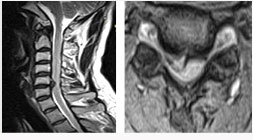

후방 요추체간 유합술 (PLIF) : 광범위한 후방 감압술 후 추간판(디스크)을 제거한 후 골이식을 시행하여 추체간 유합을 얻는 것

- 후외방 유합술에 비해 절개가 적다

- 신경근에 대한 충분한 감압이 이루어진다

- 추간판(디스크)로 인한 동통 및 재발이 없다

- 추간판 높이를 정상으로 회복시켜 준다

- 척추 정렬을 정상으로 회복시켜 준다

* 현재에는 최소 침습적인 방법으로 적은 절개를 통해 가능하다